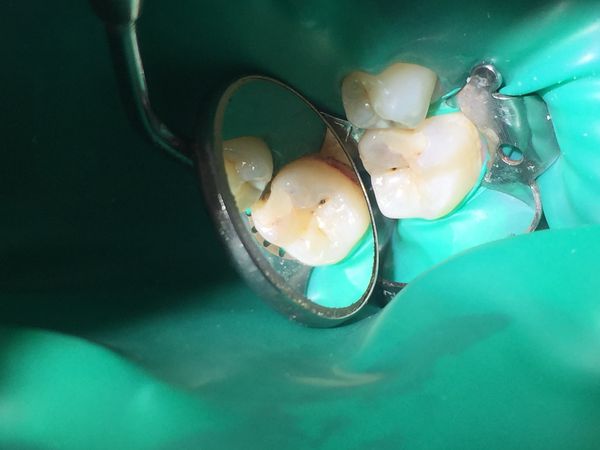

- Под анестезией сняли несостоятельную пломбу 46-го зуба с помощью алмазного шаровидного бора. Под пломбой обнаружили полость с размягчённым пигментированным дентином. Поражённый дентин удалили. После формирования полости выявили глубокий кариес на контактной поверхности соседнего 45-го зуба. Было решено в одно посещение вылечить и его.

- 45-й зуб вскрыли, удалили поражённый дентин, сформировали кариозную полость. На контактные поверхности зубов 46 и 45 положили матричные системы для восстановления боковых стенок зуба и создания контактного пункта. После этого подготовили зубы к пломбированию.